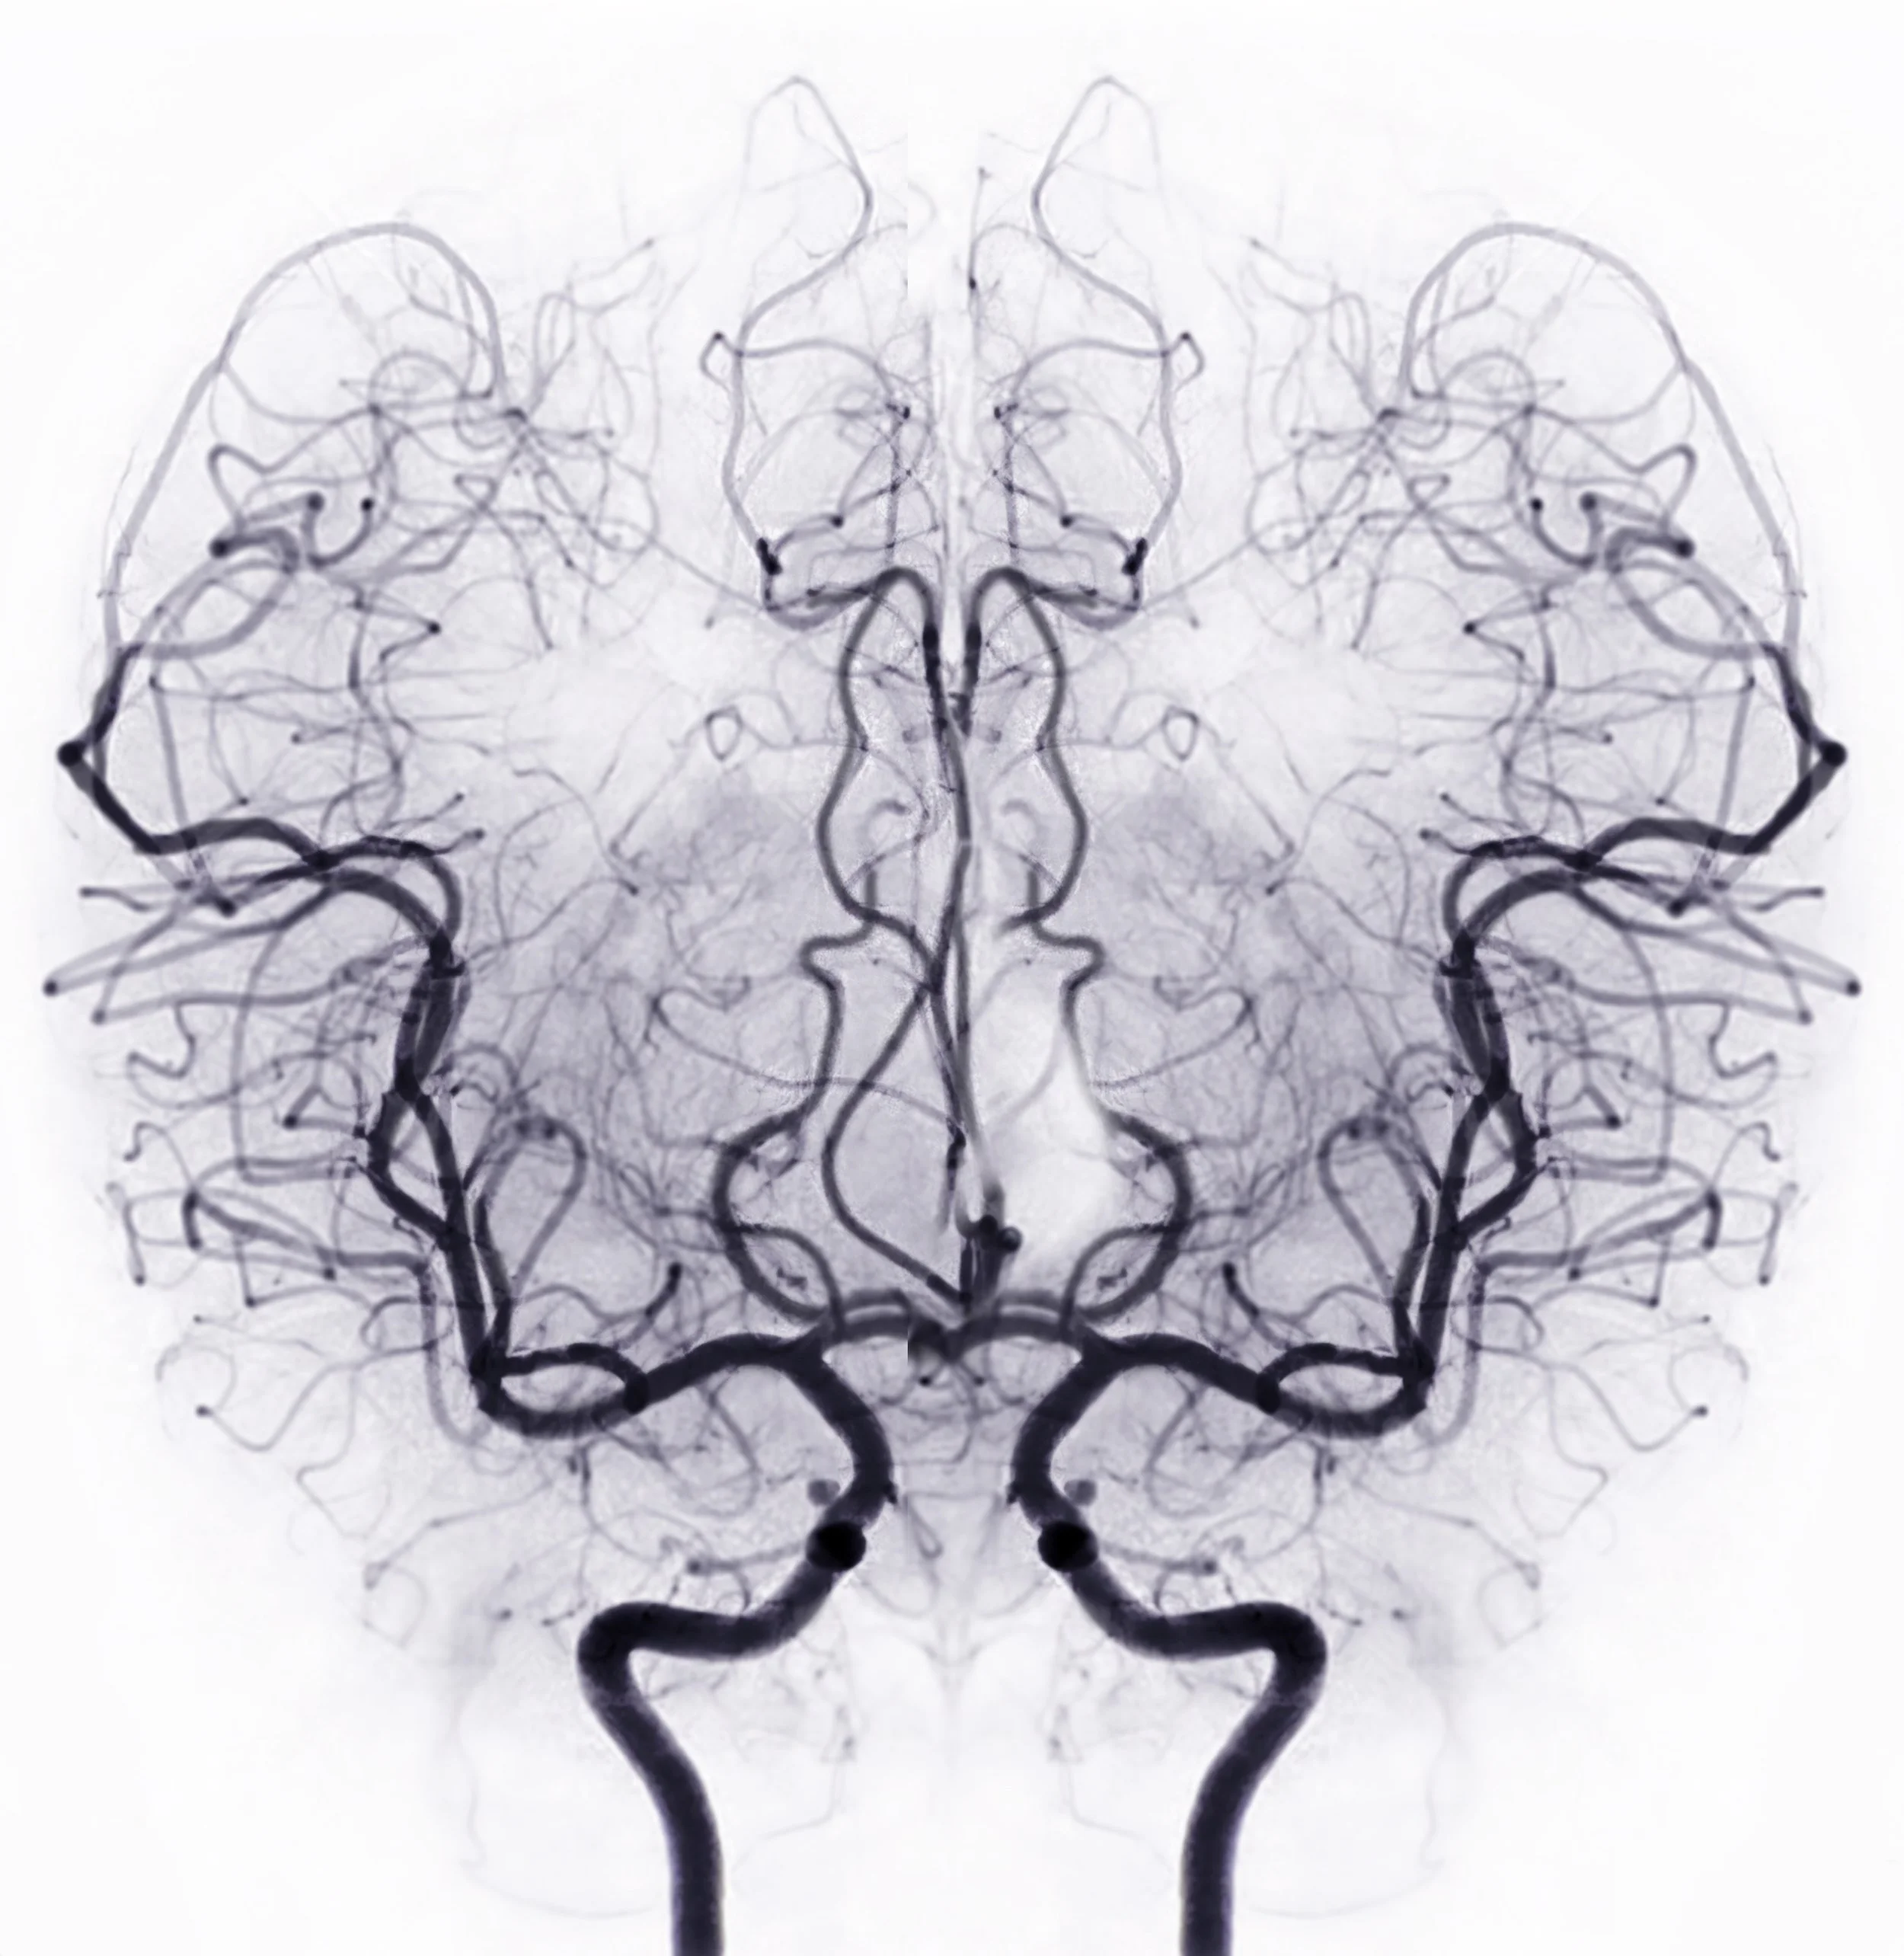

Diagnostic evaluation & minimally invasive surgery

Arteriovenous malformation (AVM)

Brain aneurysm

Dural AV fistula (dAVF)